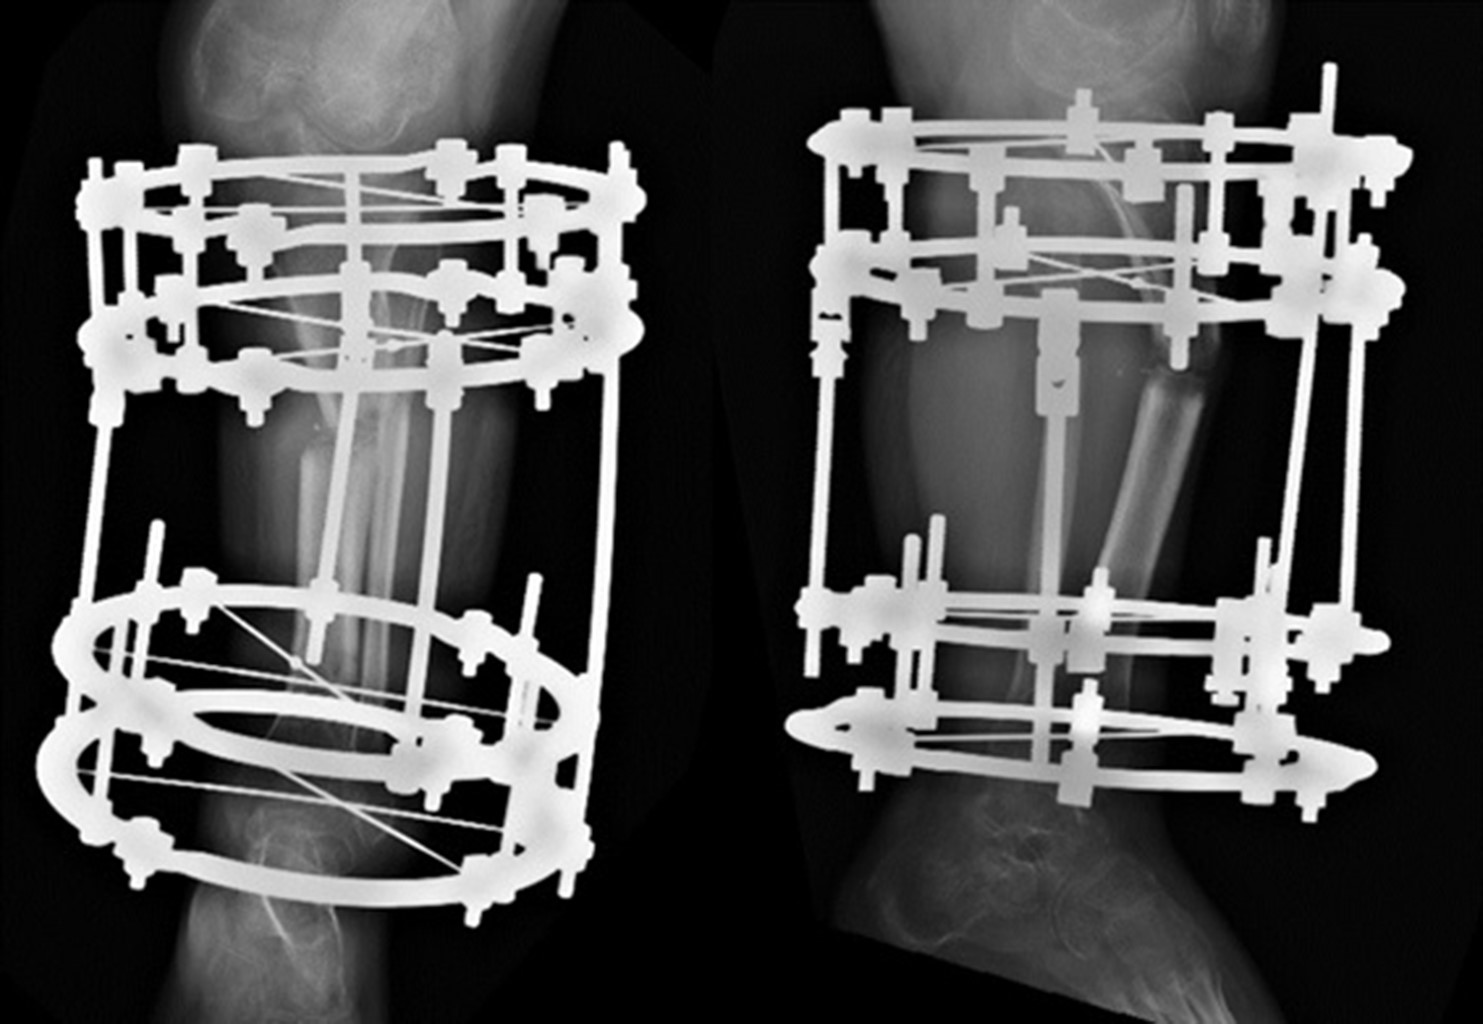

Después de 10 meses se realizó la segunda intervención quirúrgica, realizándose una osteotomía de alineación con fijador externo articulado en fémur derecho. En este sentido el objetivo fue mejorar la alineación de la superficie articular distal del fémur; la bisagra lateral, a nivel diafisario, generó una traslación, pero mejoría del eje mecánico. Continuando a la edad de 16.9 años, es decir, seis meses de la cirugía en fémur derecho, se realizó una corrección progresiva con Ilizarov en tibia izquierda, bajo el mismo principio de colocación de bisagras que en la tibia derecha (Figura 3).

La última intervención se realizó a la edad de 17.10 años, siendo osteotomía de alineación con fijador externo articulado en fémur izquierdo, donde se optó por realizar una osteotomía más distal con una cuña de apertura lateral evitando la traslación y mejorando igualmente el eje mecánico.

En su última valoración hospitalaria a la edad de 18.11 años, cuenta con una evolución clínica adecuada. Con últimas mediciones radiográficas: MAD de 30 mm derecho y 25 mm izquierdo (Figura 4).

Posterior a tres años, a la edad de 13.3 años, se realizó retiro de las placas en 8 de ambos fémures y de manera simultánea se realizó osteotomía de alineación de fémur bilateral con fijadores externos articulados.

Un año después se efectuó la tercera intervención, siendo el retiro de placas en 8, además de osteotomía de alineación y desrotadora de ambas tibias con fijador externo articulado.

A la edad de 15 años se realizó la última intervención por continuar con deformidad valga en tibia derecha. Por lo que se realizó nuevamente una osteotomía en la tibia derecha y la colocación de fijador externo articulado (Figura 6).

Figura 3

Figura 4

Figura 6